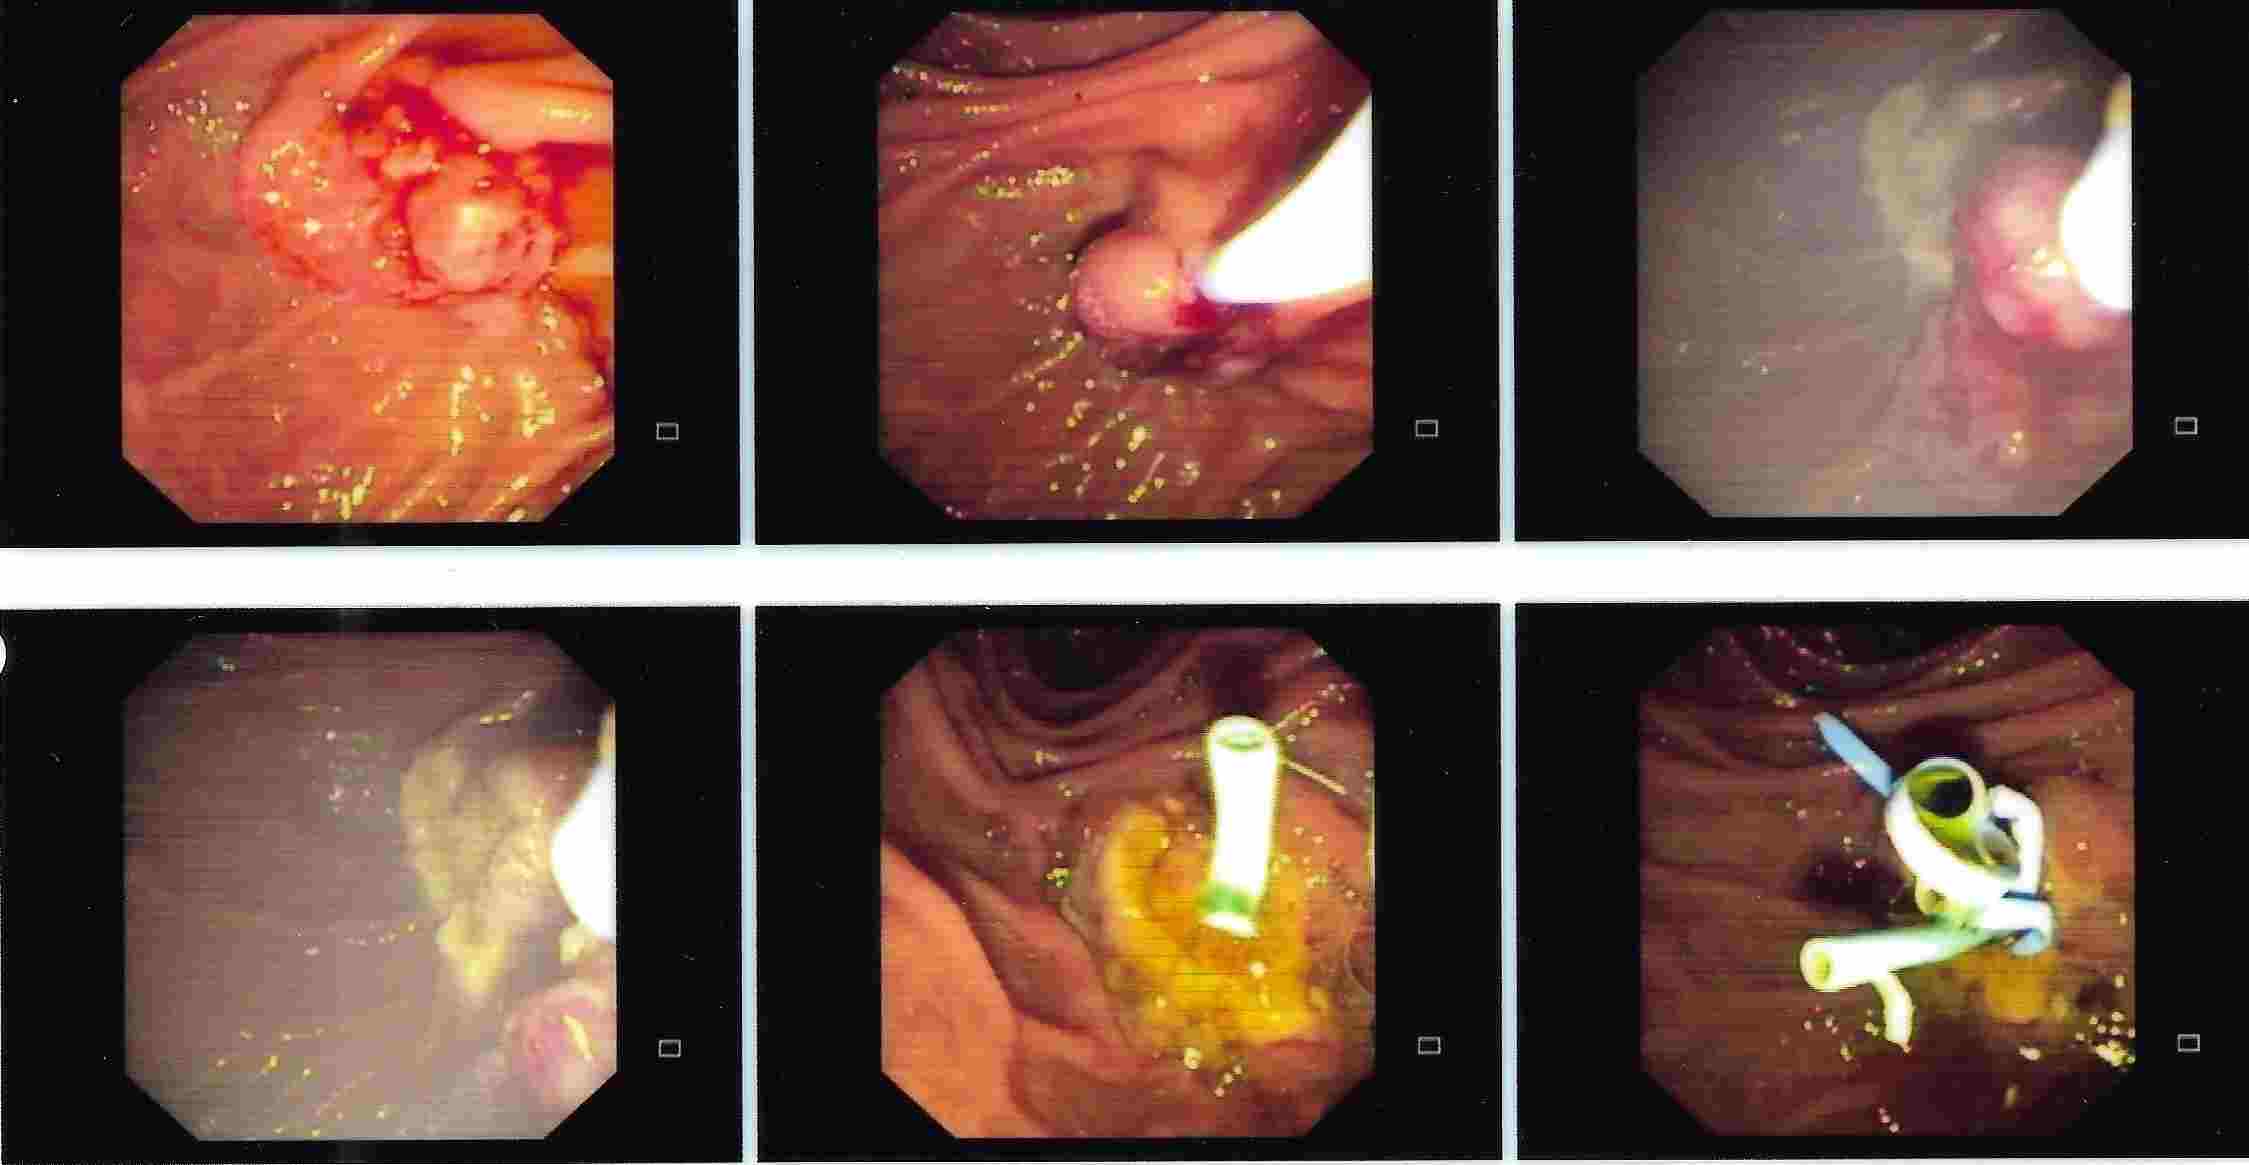

Chronic Pancreatitis is condition which can result in recurrent attacks of persistent and severe pain.

This can be due to presence of stones or narrowing of the pancreatic duct and can be treated by ERCP.

Treatment of Chronic Pancreatitis by Stent

Most of the lesions of biliary system and pancreas were treated earlier by surgery with its own complications, but now with ERCP these conditions can be treated without any surgery and morbidity and mortality related to surgery, and as a cheaper option for surgery and has become treatment of choice for the same.